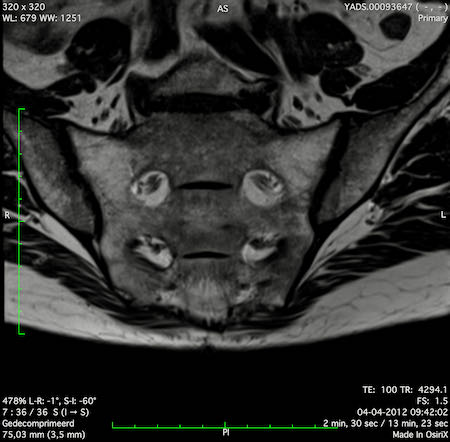

Hình ảnh

Các hình ảnh được cung cấp cho thấy ung thư biểu mô tế bào nhẫn với tình trạng dày lan tỏa thành trực tràng, hình ảnh bia bắn điển hình, và sự xâm lấn mỡ mạc treo trực tràng.